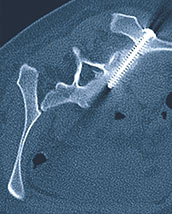

Zielvorgang einer Beckenverschraubung (Kreuzbein) mit dem Navigationssystem des Dyna-CTs an der Klinik St. Anna (Zentrum für Mikrotherapie).

Unter minimal-invasiver Becken-Chirurgie versteht man die Stabilisation von Beckenbrüchen mittels Schrauben über kleine Hautschnitte. Da das Becken in einen dicken Weichteilmantel (v. a. Muskeln) eingebettet ist und wichtige Strukturen (Gefässe, Nerven, Darm, Urogenitalorgane) durch das Becken laufen, ist es entscheidend, dass diese nicht verletzt werden. Gute anatomische Kenntnisse und die Zuhilfenahme von bildgebenden Führungssystemen sind Voraussetzung für die Operation. Das einfachste bildgebende Führungssystem ist die Röntgen-Durchleuchtung.

Bei ausgeprägter Osteoporose und bei starkem Übergewicht kann die Bildqualität mit einfacher Durchleuchtung für das sichere Platzieren der Schrauben ungenügend sein. In diesem Falle wird die intraoperative Computertomographie (CT) bevorzugt, mit der man nicht nur Schattenbilder, sondern dreidimensionale Schnittbilder erzeugt. Damit kann man auch in den Knochen hineinschauen und so im Knochen verlaufende Nerven schonen. Auf diesen Schnittbildern wird der sichere Weg der Schraube durch die Weichteile und den Knochen geplant.